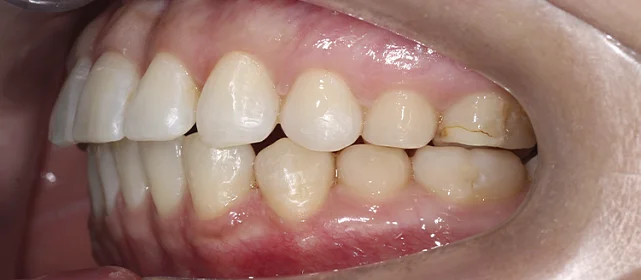

Нарушение соотношения челюстей и неправильное положение зубов — зубные ряды смыкались некорректно, зубы стояли со смещением.

Проблема: В клинику обратилась пациентка — беспокоили неровные зубы и неправильное смыкание. Зубные ряды сходились некорректно, зубы стояли со смещением, что влияло и на внешний вид, и на распределение нагрузки при жевании.